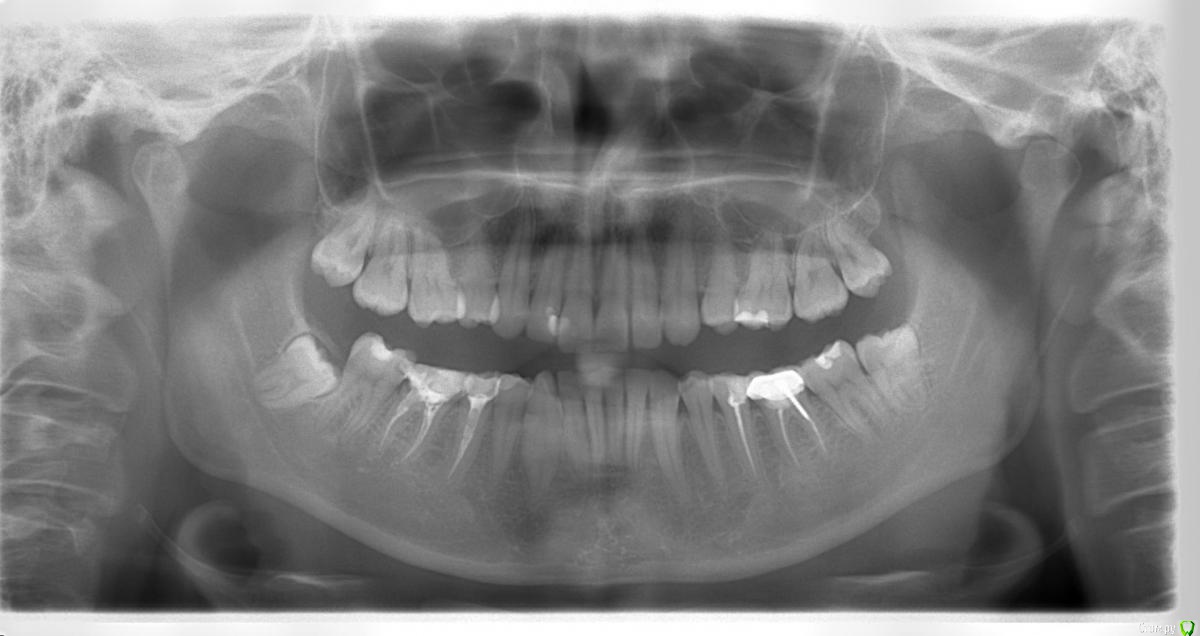

Карен Аванесов Опубликовано 18 декабря, 2015 Поделиться Опубликовано 18 декабря, 2015 Могу ошибаться, по снимкам не гомогенно запломбированы каналы (похоже временной пастой) надо им уделить внимание. Ссылка на комментарий